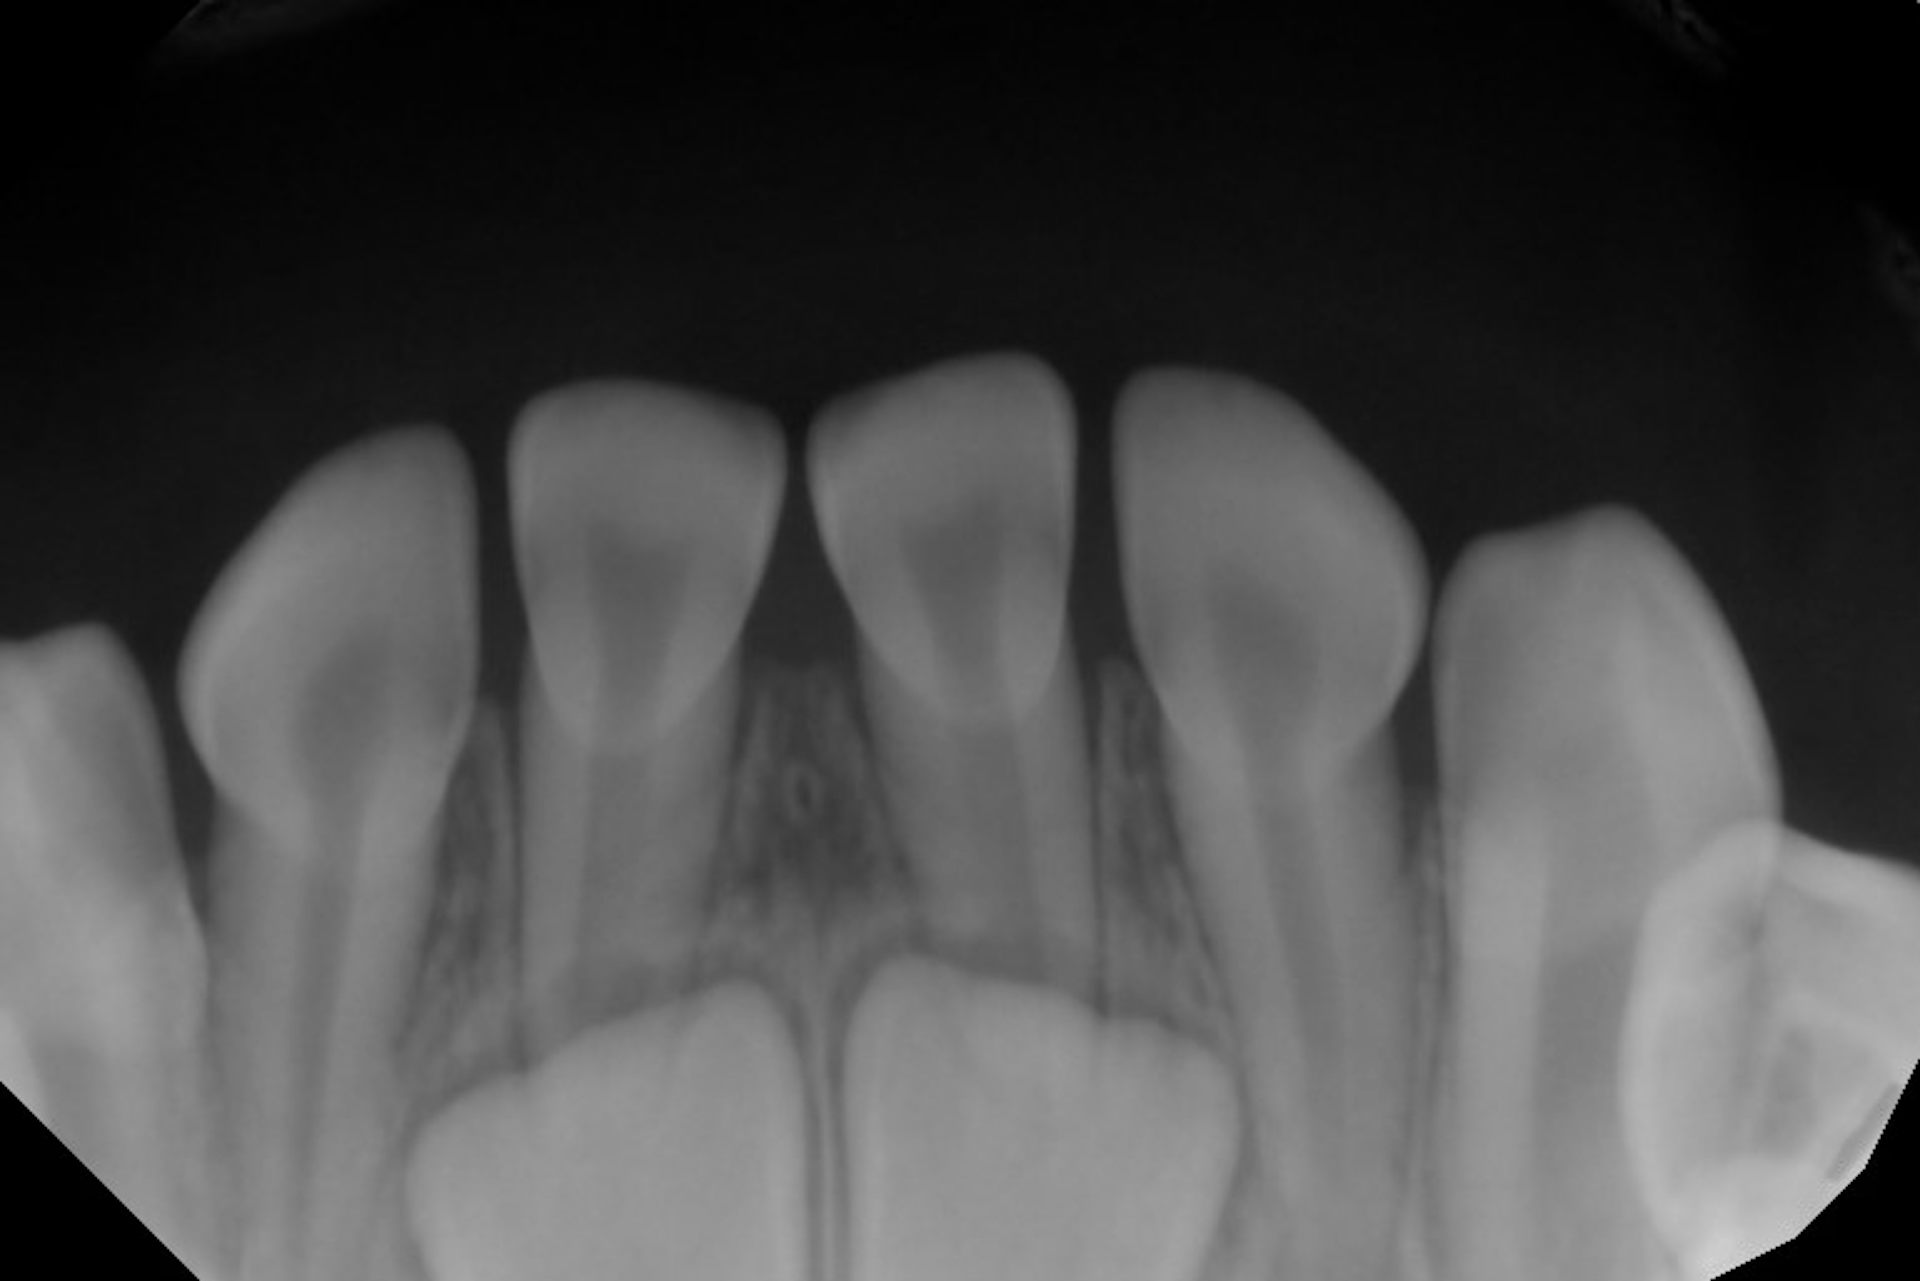

Most people are born with no teeth showing in their mouths at all, even though your baby teeth start developing before you’re even born. Baby teeth usually start poking through the gums when you’re between 6 and 8 months old. Sometimes when dentists take X-rays to check for cavities or other problems, they can see adult teeth growing within the gums.